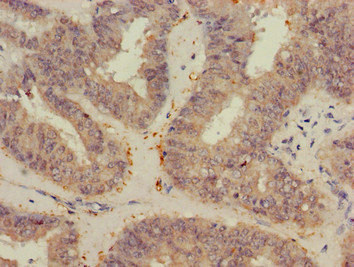

Immunohistochemistry of paraffin-embedded human gastric cancer using CSB-PA025834LA01HU at dilution of 1:100